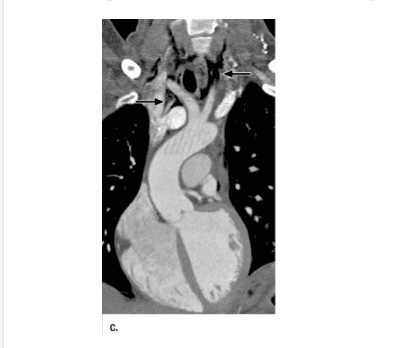

Triple-Rule-Out (viết tắt là TRO) là kỹ thuật chụp CTScan có thuốc cản quang dùng để khảo sát động mạch vành, động mạch chủ, động mạch phổi trong 1 lần chụp phim.

Kỹ thuật TRO thường dùng trong những trường hợp cấp cứu cần loại trừ các bệnh lý liên quan đến động mạch vành, động mạch chủ hoặc động mạch phổi, như thuyên tắc động mạch phổi, bóc tách động mạch chủ hoặc hẹp tắc động mạch vành.

Để chụp được kỹ thuật TRO, bệnh viện yêu cầu phải có máy CTScan từ 64 lát cắt trở lên. Máy CTScan 512 lát cắt của GE đang được sử dụng ở Vinmec Nha Trang có khả năng thực hiện tốt kỹ thuật này và không cần dùng thuốc beta blocker.